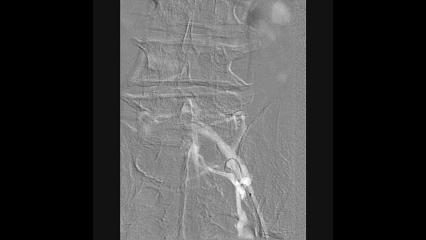

球囊扩张

使用4×150mm球囊扩张髂静脉段和股深静脉段

10mm球囊扩张左侧股深静脉、髂外静脉和髂总静脉

扩张后髂股静脉仍处于闭塞状态,有弹性回缩

支架置入

从股深静脉相对健康管腔开始

从远心端向近心端依次植入12mm支架1枚,14mm支架3枚

所有支架均为自膨式支架,近心端到达下腔静脉水平

10mm球囊对支架进行后扩